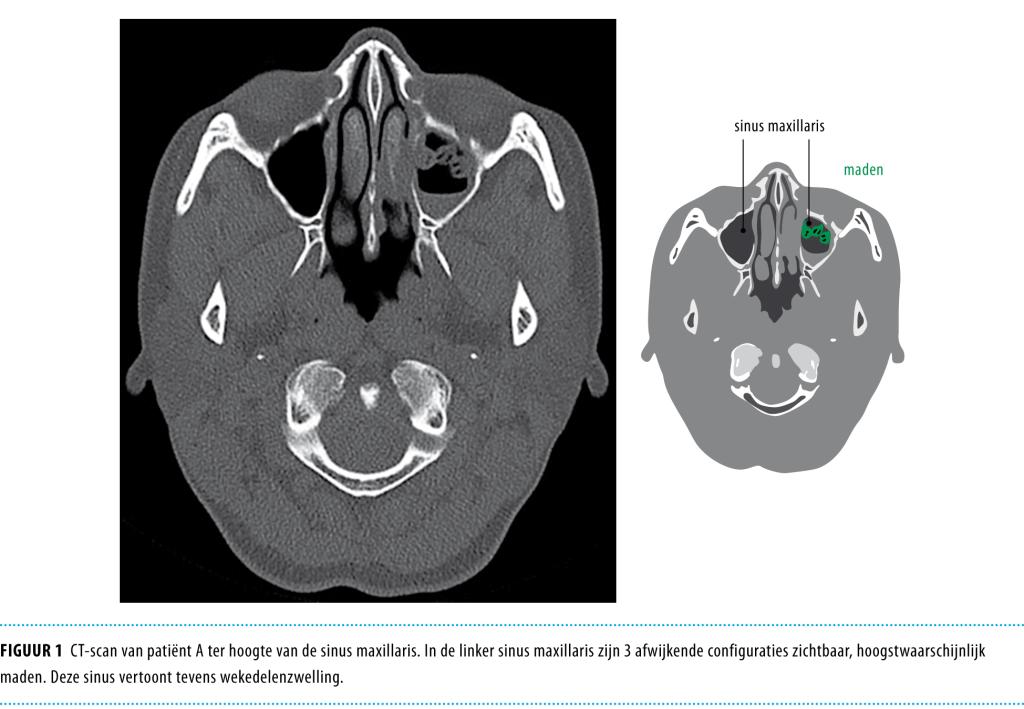

Wij beschrijven een 47-jarige vrouw die tijdens een verblijf in Kaapverdië last kreeg van niezen, een opgezwollen gezicht en een krabbelend gevoel in haar neus. Dit bleek te berusten op een infestatie van 3 volgroeide larven van de soort O. ovis in de sinus maxillaris, die door middel van endoscopie verwijderd werden.